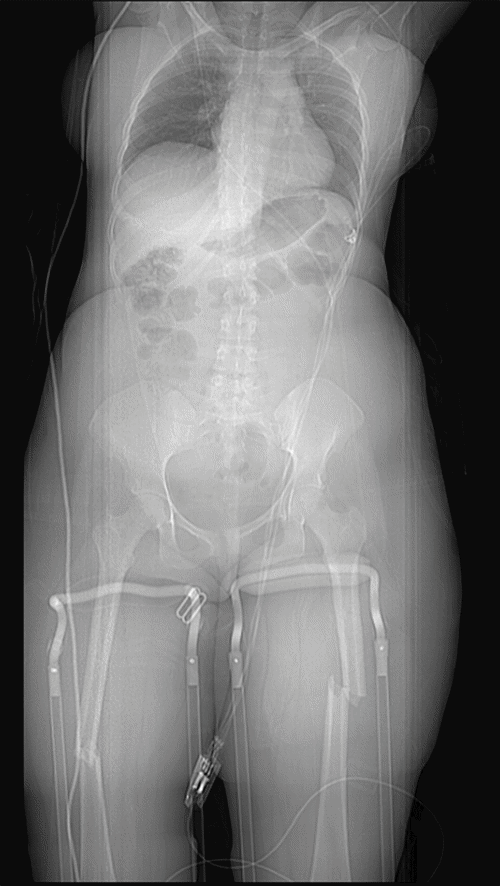

Approximately six hours after admission to the TSICU, the patient experienced an acute neurological deterioration, manifesting as right upper extremity (RUE) weakness and dysarthria. Urgent magnetic resonance imaging (MRI) of the brain was performed, which demonstrated diffuse small vessel ischemic infarcts affecting bilateral cerebellar hemispheres (Figure 3), presumed to be secondary to paradoxical fat embolization. This diagnosis was further supported by an emergent transthoracic echocardiogram, obtained immediately following the MRI, which identified a Grade 1 patent foramen ovale (PFO) (Figure 4). In light of these findings and to mitigate further propagation of fat emboli from the unstable femur fractures, the patient was taken emergently to the operating room by the Orthopaedic Surgery service for bilateral femoral external fixation, serving as a damage control measure until she achieved greater neurological stability.

Figure 3. MRI of Cerebellar Embolic Infarcts. Published with Permission

The image shows multiple, small, punctate foci of high signal intensity (arrows) distributed throughout bilateral cerebellar hemispheres, characteristic of acute embolic infarcts